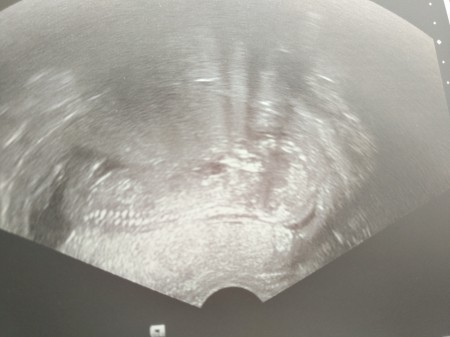

Merhaba kizlarr biraz once doktirdan geldim ama cinsiyet icin kucuk dedi. Brda bazen goruyorum tahminde bulunan arkadaslar oluyor bana tahminlerinizi yazarmisiniz. :) haftaya belli olcak testle belli oluyormus ama ozamana kadar :/ ben cok merak ediyorum.

Gebelik haftası 13+3